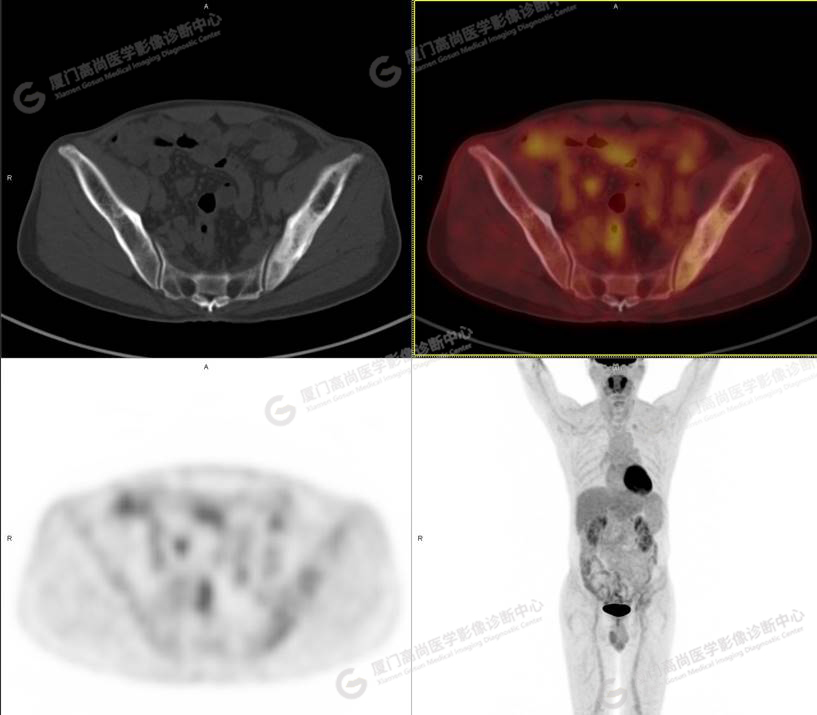

PET/CT影像圖

圖1

圖2

圖3

圖4

PET/CT所見:左側(cè)髂骨、髖臼及恥骨骨質(zhì)密度不均勻增高,CT值約594Hu,邊緣模糊,放射性攝取輕度增高,SUVmax 2.79,周圍軟組織未見明顯異常。